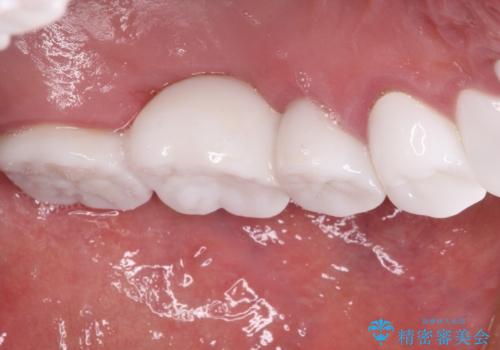

不自然なくらい真っ白にしたいとのことでしたので、透明感のないフルジルコニアクラウンを用いて補綴することとしました。

本来、あまりにも不自然な歯となるため、フルジルコニアクラウンを前歯に使用することは、咬合力が強すぎる場合を除き、ほとんどありません。

それでも、色調、形態ともに不自然なくらい真っ白な歯をご希望でしたので、患者様には大変満足していただきました。